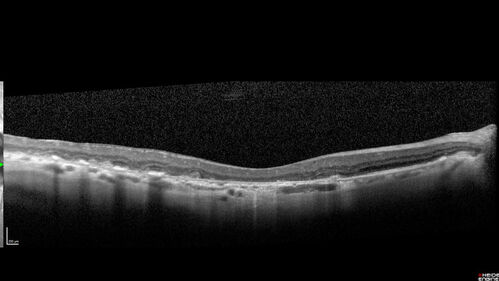

Dry AMD geographic atrophy and cystoid macular edema

79 year old vision is in for a checkup with no visual complaints in the left eye.  This is her better eye.  VA 20/200 OD, 20/50 OS.  3 years ago she had a CRVO in the left eye.  She is also diabetic for 20 years, has carotid insufficiency and anemia.  Left eye shows CME.  This was not treated and the vision improved to 20/40 over the next year although mild edema persisted.